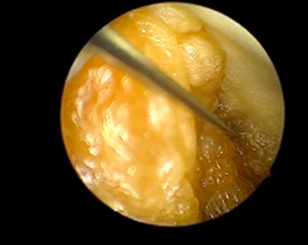

The IAT-BPM was prepared by taking a selection of bell peppers (C. annuum) and cutting a circle around the stem to detach it and clear it out (Figure 7-8). A bit of animal tissue was then secured to the underside of the cut stem using sutures, simulating a pedunculated submucous myoma and secured (Figure 9-10). The stem along with the animal tissue was then placed back on top of the bell pepper and secured with sutures.

A 5mm trocar was used to create an opening, approximately in the midsection on any one of the sides of the pepper as an entry point for the resectoscope. The model was then placed on a suitable stand, placed in a reservoir tray to collect the fluid spill. This was then placed at a convenient height with the monitor placed at a location mimicking the ergonomics of actual surgery. This model was provided at each station. The participants were provided resectoscopes with a bipolar loop electrode, connected to the electrosurgical generator set to the same parameters as actual surgery and given instructions and guidance on its assembly. The trainers emphasized the importance of correct surgical techniques like placing the loop behind the myoma and activating the energy only as the loop moved towards the operating surgeon, never away from him/her. resectoscope with a bipolar loop electrode was then used to practice myomectomy on the animal tissue and shave off bits with the correct technique, while dealing with the problems of vision caused due to bits of tissue and bubbling (Figure 12). At the end of the session, the pepper was cut in half for the trainees to inspect the result of their practice.

Figure 9: Animal tissue sutured

Figure 11: Resectoscopic Surgery